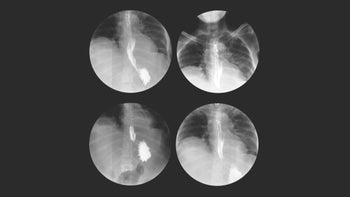

Gastroesophageal Reflux Disease (GERD) Guide: Symptoms, Diagnosis, and Treatment: Page 2